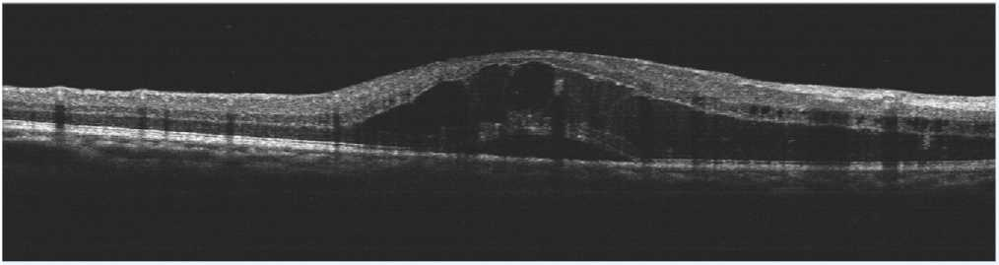

患者劉某,58歲,因右眼視力下降伴(bàn)變形1月入院。既往有高血壓病,血糖偏高病史,左眼視物(wù)不(bú)見10餘(yú)年,經過眼科主治醫(yī)師方(fāng)霏的(de)詳細檢查及(jí)眼底造(zào)影(yǐng)檢(jiǎn)查,發現是患(huàn)上了右眼視網膜分支靜脈阻塞,右眼黃斑水腫,左眼萎縮性黃斑病變(biàn)。劉大叔入院時右眼視力僅0.1 ,需要使用一種新型的生物製劑(jì)(抗 VEGF)治(zhì)療,方霏主治醫師向患者及(jí)家屬交代病情、手術(shù)必要性及相關風險 ,在排(pái)除(chú)了手術禁忌症後,患者及家屬表示同(tóng)意手術治療。次日,方霏主治醫師在患者(zhě)表麵麻醉下進行右(yòu)眼(yǎn)玻璃體藥物注射術,術後患者(zhě)無明顯特殊不適。4周後複查,右眼黃斑水腫明顯減輕,視力由0.1提高至0.6。玻璃體腔注藥術明顯改善了患者視力,患者劉大叔表示十分滿意。

術前OCT檢查提示右眼黃斑水腫

術後OCT檢查提示(shì)右(yòu)眼黃斑神經上皮層厚度較前(qián)明顯變薄